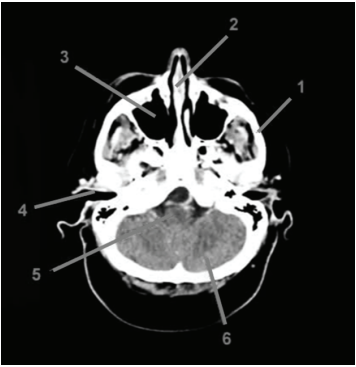

A realização de exames radiológicos permite a obtenção da imagem de formações internas do corpo, sendo possível avaliar a presença de tumores, fraturas, sangramentos, corpo estranho ou qualquer outra anomalia. Analisando a imagem abaixo, assinale a alternativa CORRETA: